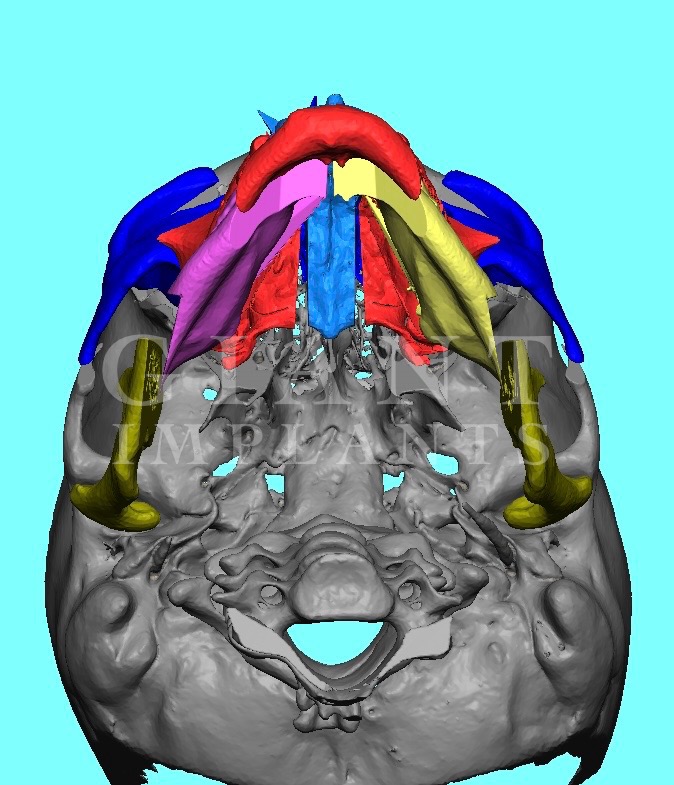

Yo @RealSurgerymax what your opinion on zso to widen face here’s example of eppley

IMG 3239

IMG 3240